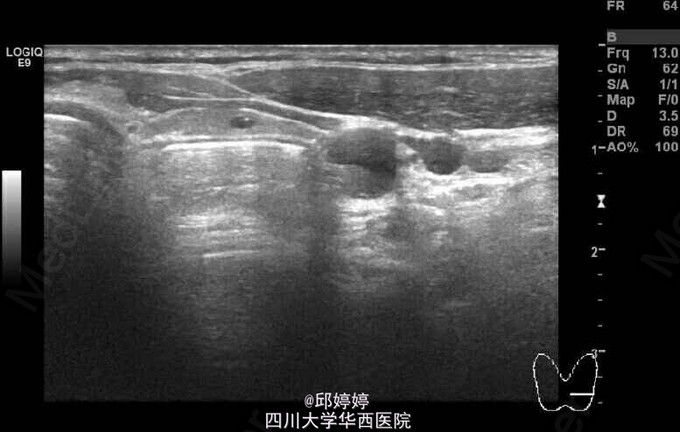

患者,女,60岁,无特殊不适,行常规体检。超声检查发现患者颈部甲状腺左侧叶后方查见大小约23x9mm的杂乱回声团,内可见气体样强回声,后方回声衰减(图1-3)。 诊断:食管憩室。 此种现象较为少见,应注意与甲状腺本身的病变相区别,以防误行进一步的穿刺活检而导致食管损伤。